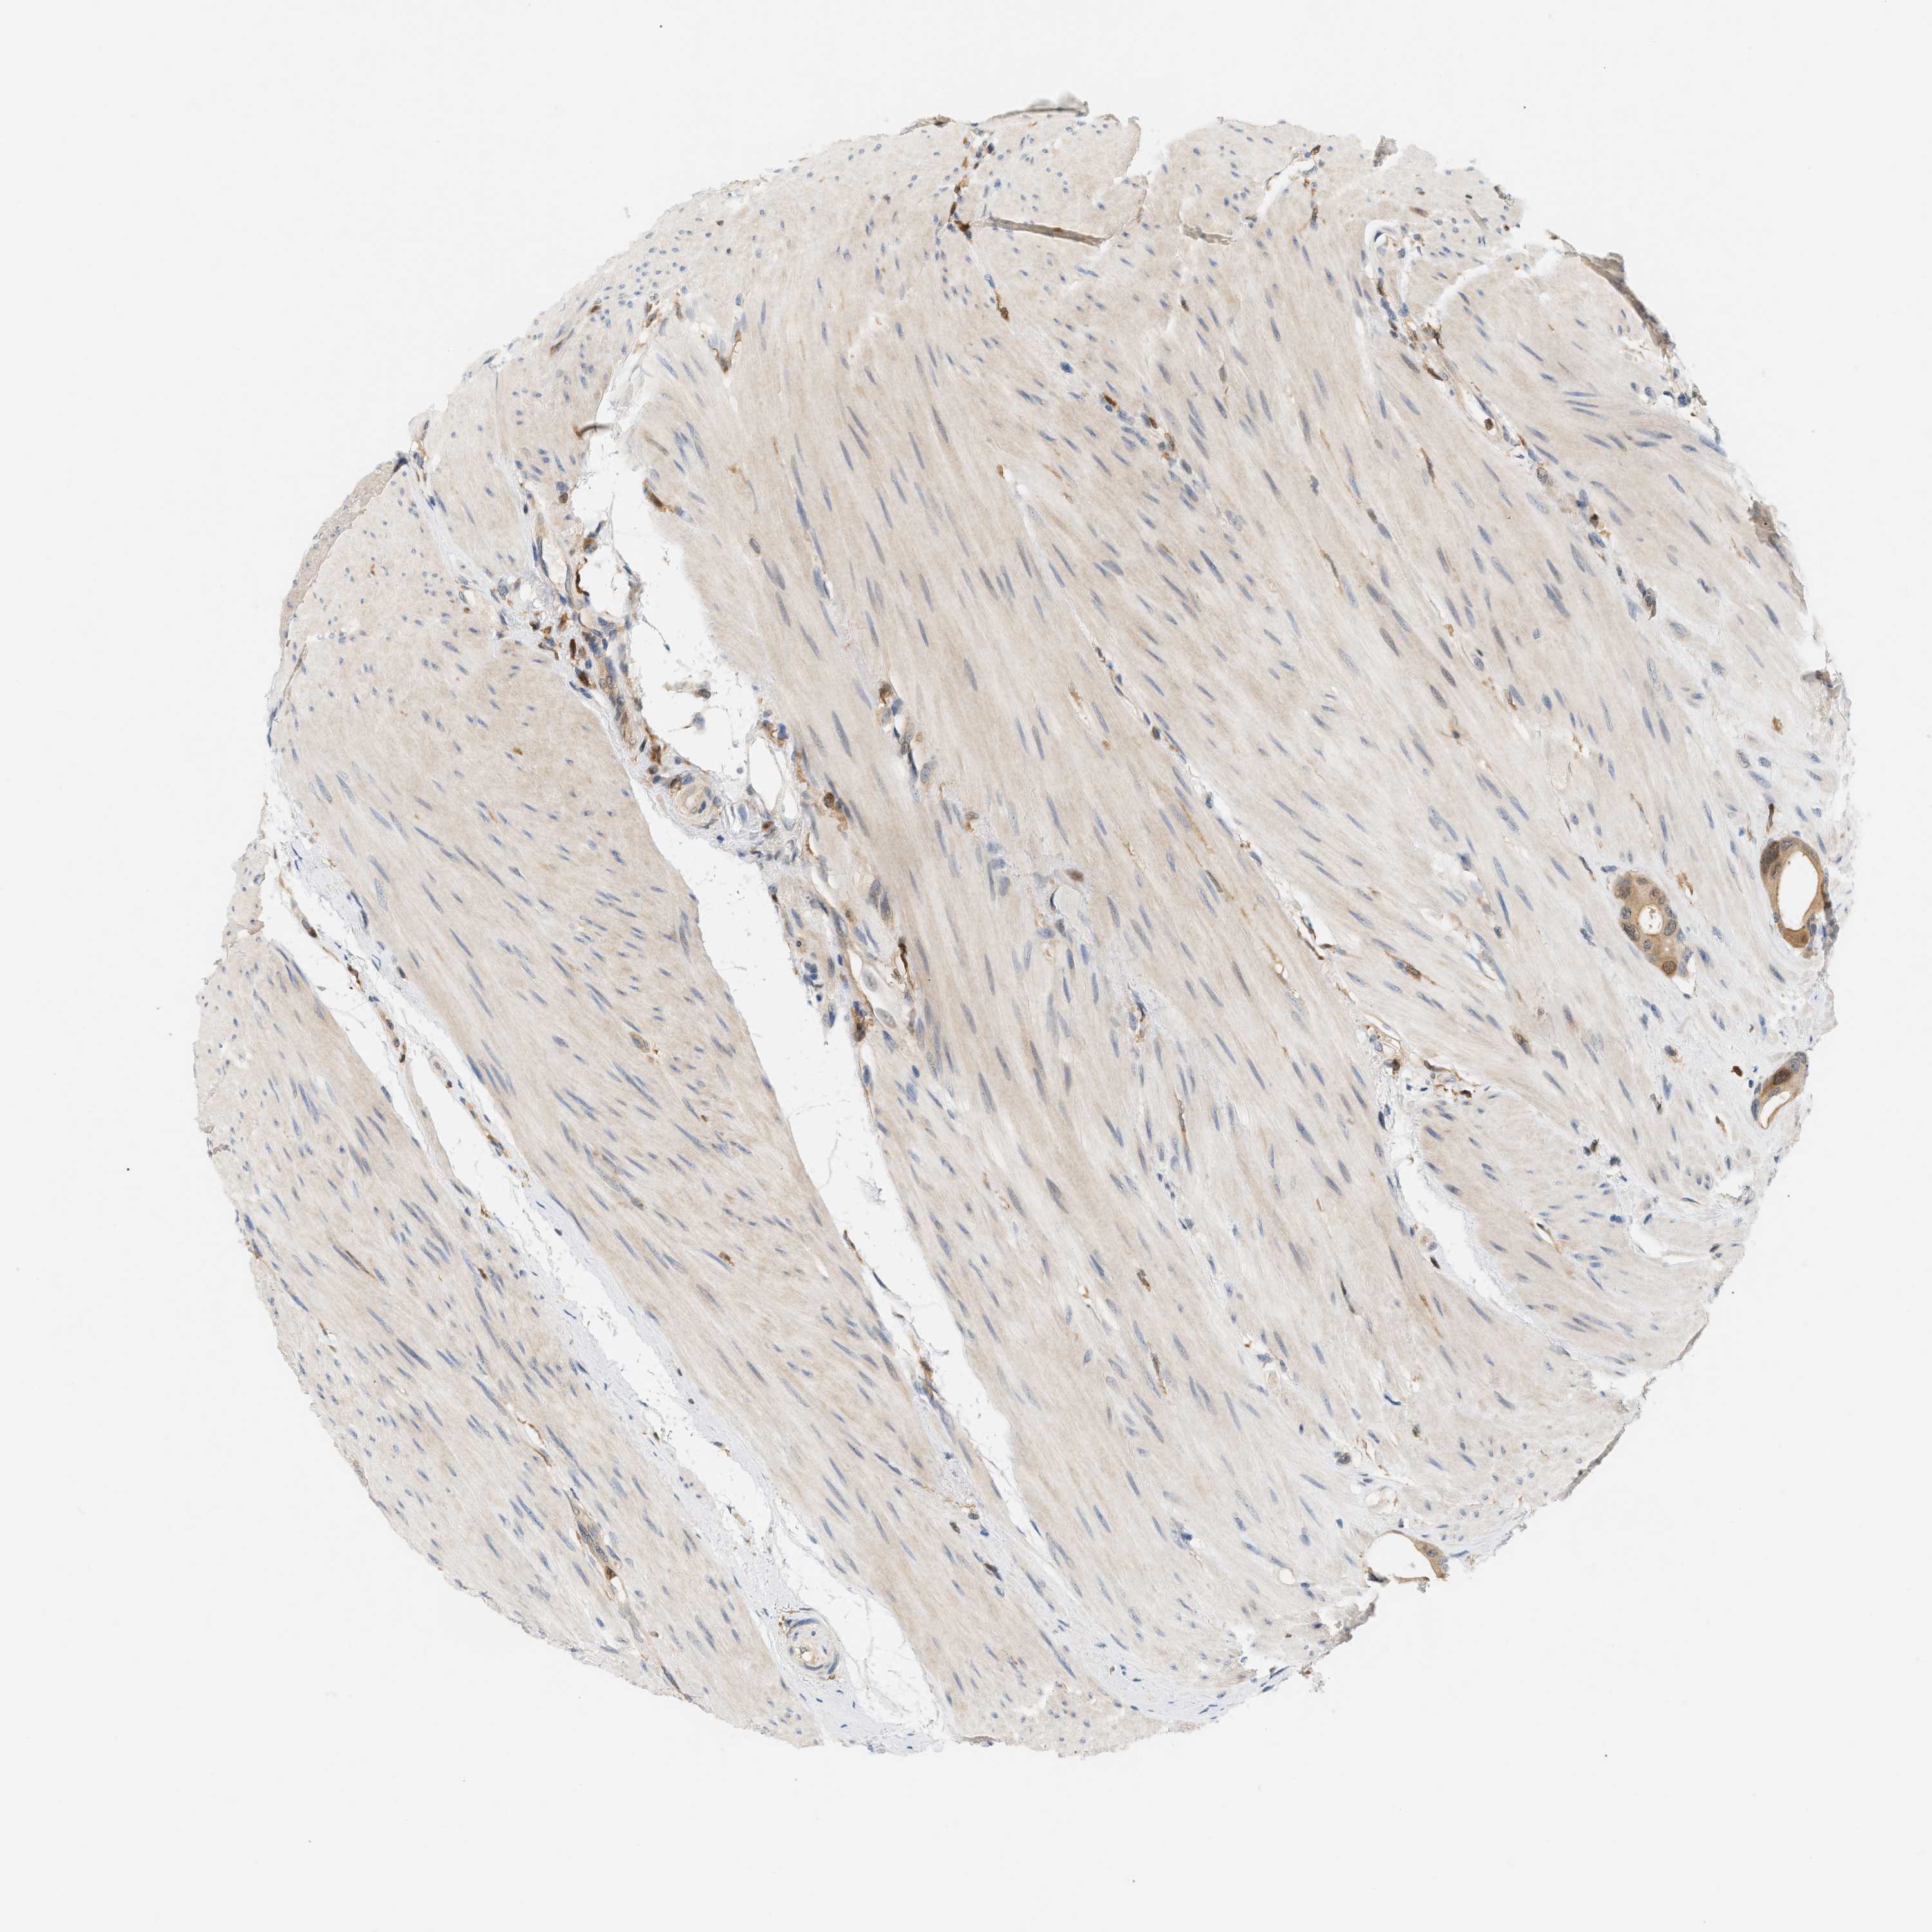

CANCER COLORECTAL CANCER Show tissue menu

Colorectal cancer

Human cancer